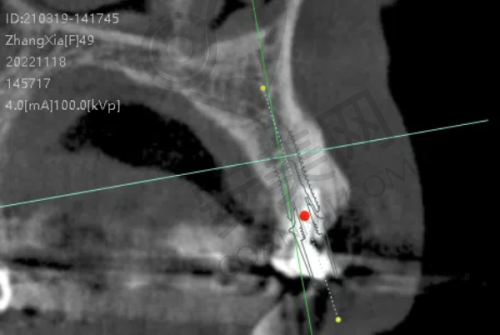

李明医生则在口腔种植领域有超过15年的临床经验,擅长各种种植牙技术,包括即刻种植、All - on - 4种植等。医生们术前会根据患者咬合关系、骨条件定制方案,避免“一刀切”式治疗;通过严格术前检查(如CBCT扫描)和术中导航,减少神经损伤、感染等并发症;术后还会提供定期随访服务,延长种植体使用寿命。